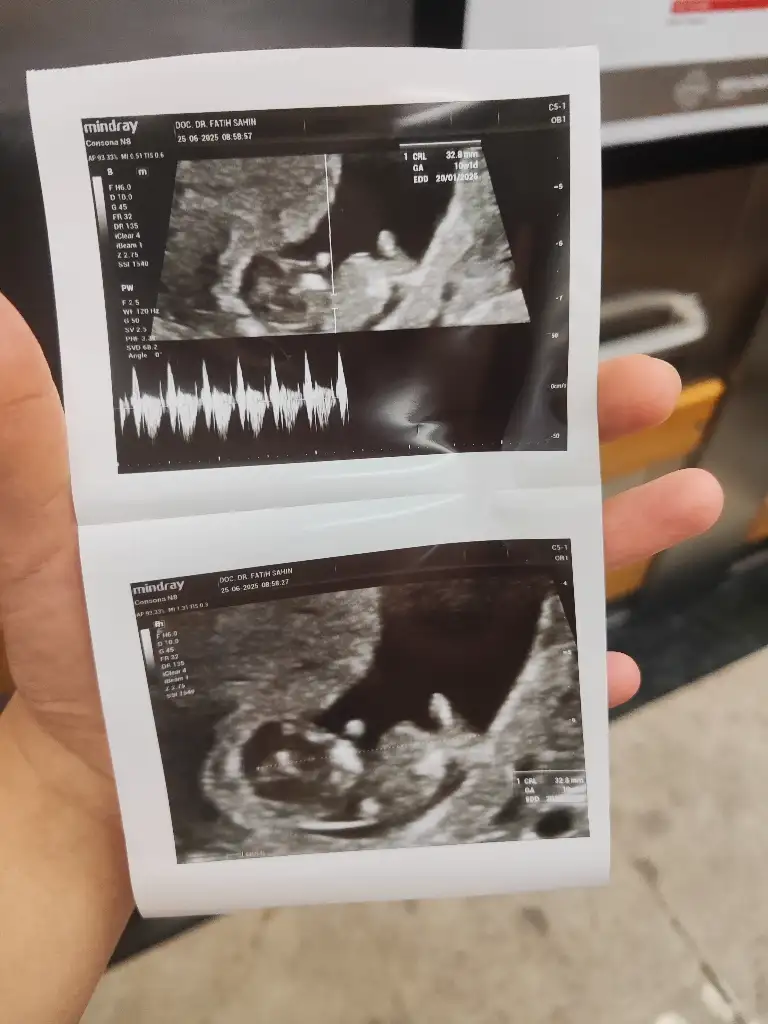

Maşallah ne kadar büyümüş bende 10.haftama gireceğim böyle mi görünecek yaa çok duygulandimKızlar benim randevum cumartesi günüydü ben dayanamadım biraz karnım ağrıyor diye bu sabah gittim.

Muhtemelen klimadan falan üşüdüm ondan ağrıyor çünkü bir problem yok.

Telefondaki uygulamam da 10+4 bugün.

Ultrasonda 10+1 çıktı.

Bir hafta sonra tekrar kontrole bekliyor beni.

Bebiş bayağı büyümüş ultrason fotoğrafını bırakıyorum size.

Bugün hareket etti ultrasondaelini kolunu bayağı hareket ettiriyor Şok oldum çok duygulandım.

Elindeki folik asit bittiğinde sana bir multivitamin yazıyorum ona başla folik asite devam etme dedi. Omega 3 tabanlı bir multivitamin. Femival Vita yazıyor kağıtta daha almadım.

6 haftadan beri mide bulantısı için prilam kullanıyorum ona devam et kesme dedi.